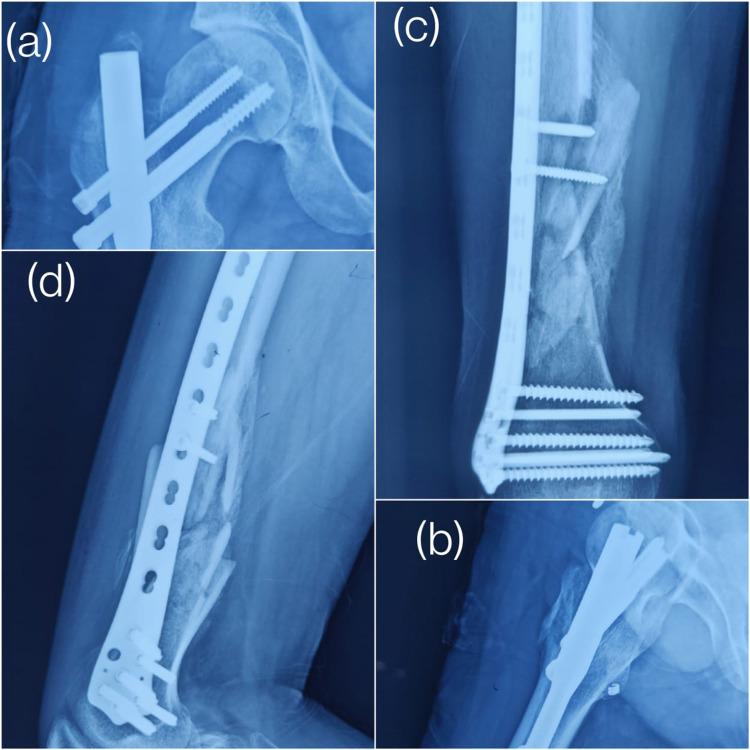

Introduction Most surgeons prefer a single implant for segmental proximal and diaphyseal femur fractures, although results are controversial and still no consensus for proper management is present. This prospective study analyses the functional and radiological outcome of managing 17 patients with ipsilateral shaft and proximal femur fractures by dual implant osteosynthesis at our center. Methods Over a two-year period, we managed 17 patients with a mean age of 35 years, with cancellous cannulated screws or dynamic hip screws for intracapsular femur fractures and improvised proximal femoral nail for extracapsular proximal femur fractures. Distal femoral locking plates or distal femoral nails were used for shaft femur fractures depending upon fracture morphology. The patients had a maximum follow-up of 18 months. Results A total of 80% of patients had a good functional outcome (using the Friedman-Wyman scoring system) while 60% had an excellent Harris Hip Score. The mean time taken for the bone union for proximal femur fractures was 4.75 months and for shaft femur fractures, it was 6 months. Conclusion We had a satisfactory functional and clinical outcome of managing these fractures with two implants, one focusing biomechanically on each fracture. This principle of dual implant osteosynthesis can reliably be used in such difficult fracture patterns and it negates the use of the single cephalomedullary nail for fixating both fractures.

引言 大多数外科医生倾向于使用单一植入物治疗股骨近端和骨干的节段性骨折,尽管结果存在争议,且对于合适的治疗方法仍未达成共识。本前瞻性研究分析了在我们中心采用双植入物接骨术治疗17例同侧股骨干和股骨近端骨折患者的功能和影像学结果。方法 在两年时间里,我们治疗了17例平均年龄为35岁的患者,对于股骨颈骨折采用松质骨空心螺钉或动力髋螺钉,对于股骨近端囊外骨折采用简易股骨近端髓内钉。根据骨折形态,股骨远端骨折采用股骨远端锁定钢板或股骨远端髓内钉。患者的最长随访时间为18个月。结果 共有80%的患者获得了良好的功能结果(采用弗里德曼-怀曼评分系统),而60%的患者获得了优秀的哈里斯髋关节评分。股骨近端骨折的平均骨愈合时间为4.75个月;股骨干骨折的平均骨愈合时间为6个月。结论 我们采用双植入物治疗这些骨折取得了令人满意的功能和临床结果,每个植入物在生物力学上针对一处骨折。双植入物接骨术的这一原则可可靠地用于此类复杂骨折类型,并且无需使用单根髓内钉固定两处骨折。